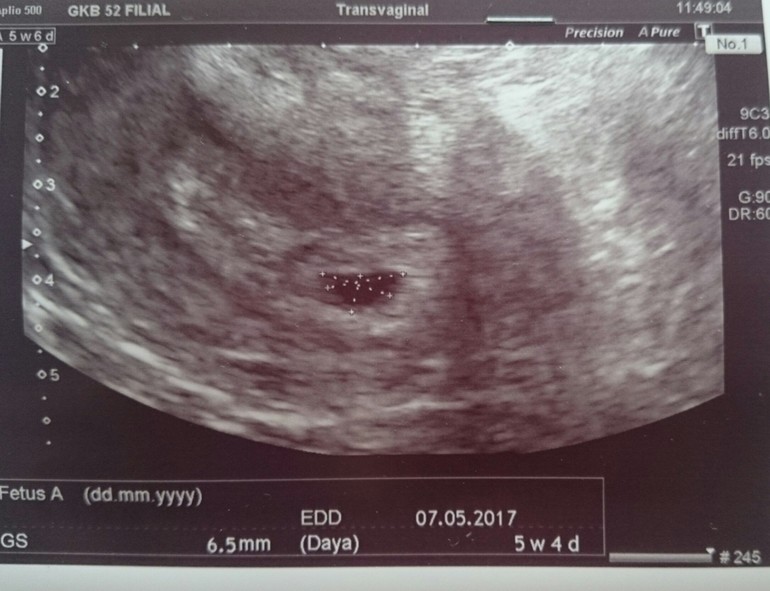

Впервые увидела бусинку

Направили на узи, но в ЖК такая очередь на 2-3 недели, что решила идти в платную. Там показали бусинку 6,5 мм) все наше) контрольное узи через 2 недели, чтобы услышать сердечко 💜